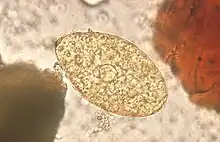

The eggs (ova) of Echinostoma are operculate [4] and vary in size, but are typically in the range of 80-135μm × 55-80μm.[7]

An Echinostoma ilocanum egg (larger arrow) -

An Echinostoma infection can be diagnosed by observing the parasite eggs in the faeces of an infected individual, under a microscope. Methods such as the Kato-Katz procedure can be used to do this.[3] The eggs typically have a yellow-brown appearance, and are ellipsoid in shape.[20] To confirm which species is causing the infection adult worms must be recovered from the infected individual, such as with anthelmintic treatment.[20]